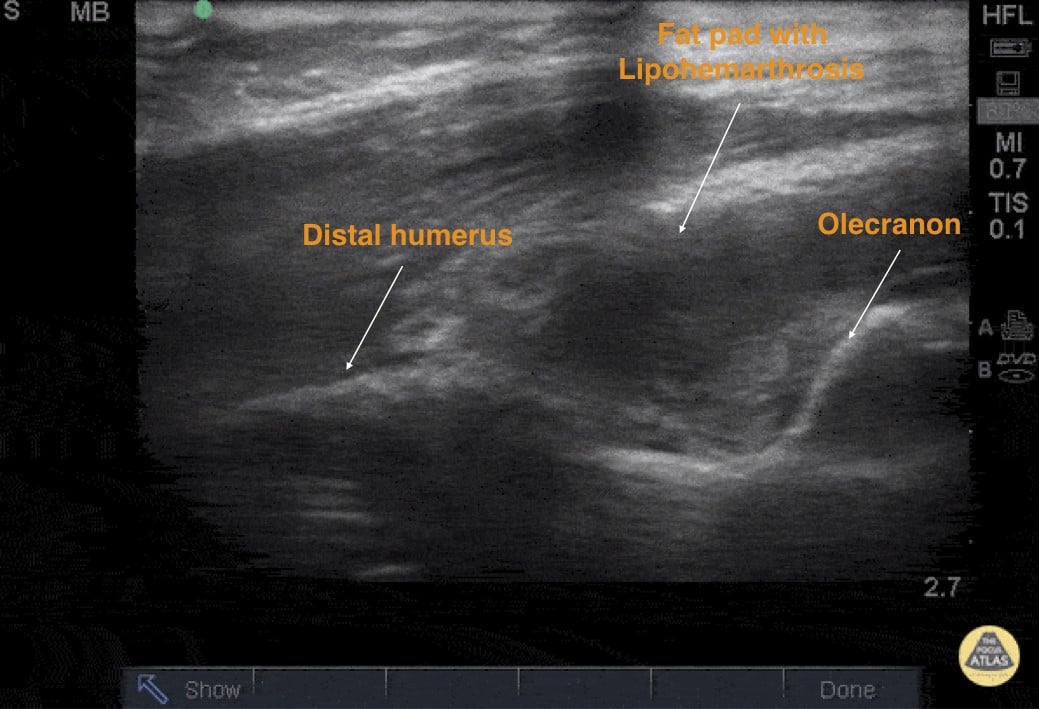

Bulging posterior fat pad: rise of the fat pad (Sail sign) above the extension of the distal humeral line on longitudinal view (Figure 4) or above a line connecting both lips of the olecranon fossa on transverse view (Figure 5).

Lipohemarthrosis: heterogeneous echodensity with hypoechoic areas of the posterior fat pad

Figure 4: Longitudinal axis of the elbow depicting an area of elevated fat pad with Lipohemarthrosis (hypoechoic, with fluid) that is concerning for a supracondylar fracture. Image credit: Pocus Atlas